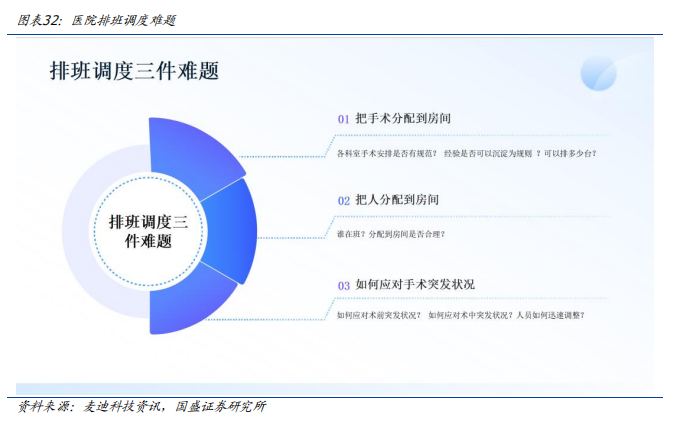

麦迪产品AI+数字调度,重构手术室资源分配。麦迪科技在进行深入的市场调研过程中,细致地访问了多家医院,通过与医护人员的交流和观察,详细了解了他们在手术室排班调度方面所面临的各种挑战。经过这一系列的调研工作,麦迪科技梳理了手术室排班调度的三大核心问题:首先,如何合理地将各种手术分配到不同的手术间,以确保手术的顺利进行;其次,如何有效地将医护人员分配到各个手术间,以保证手术团队的高效协作;最后,如何制定应对策略,以应对手术过程中可能出现的各种突发状况,确保手术的安全高效进行。

建设手术排班调度系统。基于当前手术室排班调度痛点与难点,麦迪科技围绕围术期手术排班调度的管理,引入手术申请、手术审核排班、手术室统筹、消息通知、知识库、信息管控的概念,建设一套手术排班调度系统。系统与麻醉系统、HIS系统关联,形成护理组排班—麻醉组排班—手术申请—手术室统筹排班—手术安排通知—手术实时调度—病区接患者—这一套手术闭环流程。

l全新引入预排台机制:改变现有的排班模式,将临床科室的实际需求做为手术排班的重要参考因素,从而提升医护人员满意度。

l人员智能排班:高效地将主刀医生、手术室护士、麻醉医生以及患者等相关人员紧密联系起来。通过多班种分组设定、多样化的递进轮班规则、节假日与请假管理等功能,大大提高了人员排班的效率和准确性。

l智能分配规则引擎:在原先人工排班调度的基础之上,运用人工智能技术及算法,构建应对医院复杂业务场景的智能规则引擎,达成全智能手术分配与人员排班,解决了手术排班计划脱离实际,无法有效指导实际工作的问题。

l手术时长预测模型:依托精准手术时长预测与实时消息推送,辅以智能调度算法决策推荐,系统将手术间的医护、患者、设备、物资有序联结,最大程度提高手术间利用率与周转率,均衡资源分配,实现手术间高效协同运转,切实提升手术间服务质量与管理运营水平,增强医护人员获得感,从而最终达成为患者提供更高质量、更高效率、更加安全、更加体贴的医疗服务的终极目标。

l动态规划、贪心算法提供最优手术调度方案:动态规划的算法与贪心算法实时计算负荷不均匀的手术间,并结合手术间规则、手术间人员排班情况等给出对应合理建议调整手术所分配的手术间,从而使手术间的整体利用率达到相对均衡的状态。